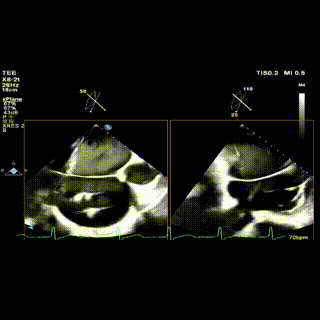

2区

怎么上穿刺鞘攻克巨大左房伴转位穿刺难关!温医大附一院周浩教授团队创新应用“导丝定位+可调弯鞘”技术完成高难度TEER手术_https://www.jmylbn.com_新闻资讯_第5张

2区带彩

怎么上穿刺鞘攻克巨大左房伴转位穿刺难关!温医大附一院周浩教授团队创新应用“导丝定位+可调弯鞘”技术完成高难度TEER手术_https://www.jmylbn.com_新闻资讯_第6张

1.二尖瓣重度关闭不全(4+),瓣环明显扩大(AP径4.6cm,LM径3.9cm),扁平,关闭时瓣叶对合不佳(carpentier I),1-3区均可见反流束,返流宽度达26mm;肺静脉频谱呈收缩期反向。

2.画迹法测得二尖瓣瓣口面积约8.8cm²。

3.PISA法测得EROA=0.57cm²,Rvol=77ml,r=11mm。

4.二尖瓣前叶(A2)长度29mm,后叶(P2)长度11mm。

5.左房巨大(三径86*84*114mm),右房巨大(内径114*86mm),CFI提示极重度三尖瓣反流,Teich法测得EF为70.1%。